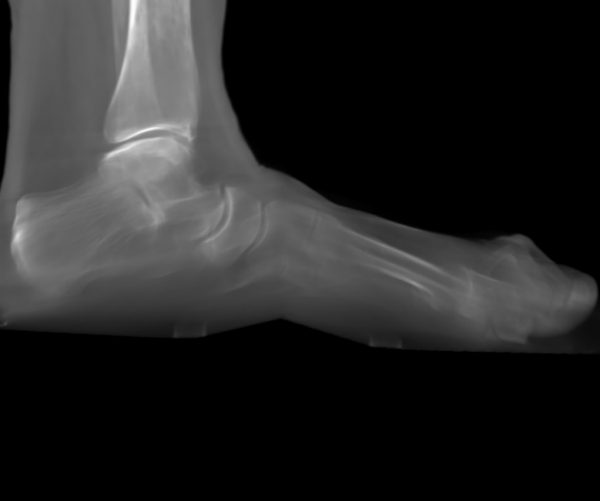

Arthrose oder Fehlstellung im unteren Sprunggelenk schränkt vor allem das Gehen auf unebenem Untergrund schmerzhaft ein. Wenn konservative Maßnahmen nicht mehr ausreichen, ist die Versteifung das zuverlässigste Verfahren für Schmerzfreiheit und stabile Belastbarkeit. Wenn Sie noch abwägen ob eine Operation notwendig ist: Arthrose unteres Sprunggelenk – Ursachen & Therapie

Das untere Sprunggelenk besteht anatomisch aus drei Teilgelenken — dem hinteren talo-calcanearen Gelenk (zwischen Sprungbein und Fersenbein), dem talo-navikularen Gelenk (zwischen Sprungbein und Kahnbein, Os naviculare) und dem calcaneo-cuboidalen Gelenk (zwischen Fersenbein und Würfelbein). Je nach Ausmaß des Befunds werden eines, zwei oder alle drei Teilgelenke versteift.

Das Ziel der Operation ist ein stabiler, dauerhaft schmerzfreier Rückfuß unter Alltagsbelastung. Die wichtigste Einschränkung bleibt die reduzierte Ausgleichsbeweglichkeit auf unebenem Untergrund — die Ausgleichsbewegungen nach innen und außen, für die das untere Sprunggelenk zuständig ist, sind nach der Arthrodese aufgehoben. Ebenes Gehen, Radfahren und Schwimmen sind in aller Regel gut möglich. Laufen auf unebenem Untergrund bleibt eingeschränkt.